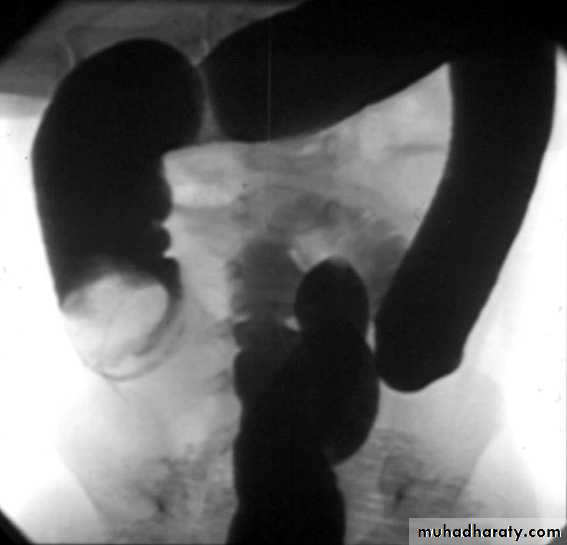

Clinical US Contrast Olive mass studyFeed test

3. Contrast enema